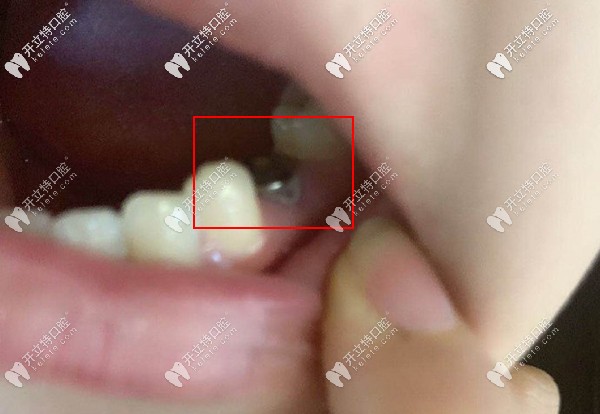

看看種植后的牙齒效果,擁有一口好牙真的是太nice了。

看看種植后的牙齒效果

種植反饋:主要是缺失的是咀嚼用的主要牙齒,還是要種上才能當(dāng)個(gè)快樂吃貨,選擇正規(guī)的醫(yī)院靠譜的醫(yī)生尤為重要,當(dāng)初她也是做了很多功課才選擇來(lái)德韓。